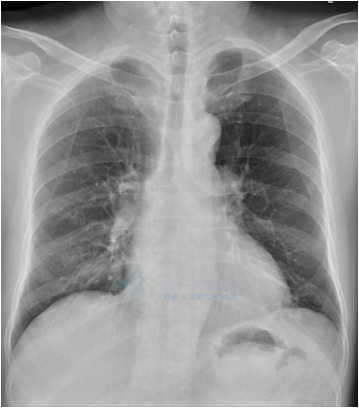

两肺纹理增重

心影增大